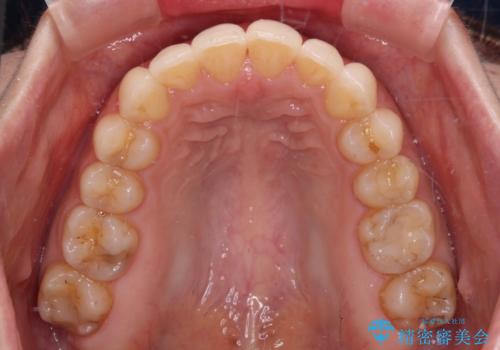

- 上下の前歯のデコボコを気にして来院された患者様です。

妊娠中であり、途中通院が難しくなる可能性があることから、インビザラインによる矯正治療を行うこととしました。

上下顎歯列全体の後方移動とIPR(歯と歯の間を削る)によってデコボコが解消するように設計しました。